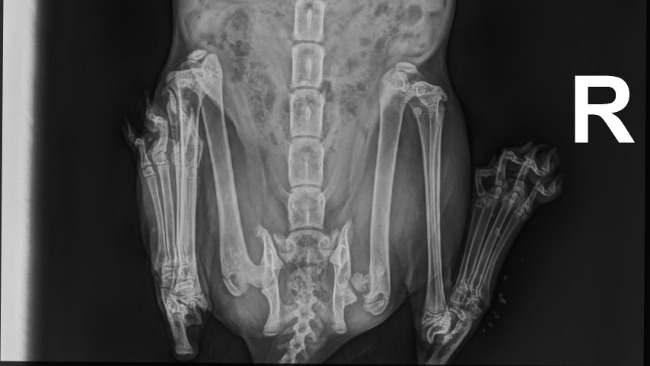

Jednak Ciotki szybko zauważyły, że koteczka kuleje, a na ogonie są ranki i jest częściowo bezwładny. Na konsultacji u internisty zrobiliśmy RTG i niestety okazało się, że koteczka musi być po wypadku - główka kości udowej jest w pełni odłamana :(

Pełna diagnostyka, operacja polegająca na resekcji główki kości udowej i amputacja ogona zostały wycenione na 3500 złotych... To duża suma dla nas w tym momencie, szczególnie że ostatnio sfinansowaliśmy kilka zabiegów dla kotów wolno żyjących w Warszawie (o tej porze roku nie ma już pieniędzy miejskich :(